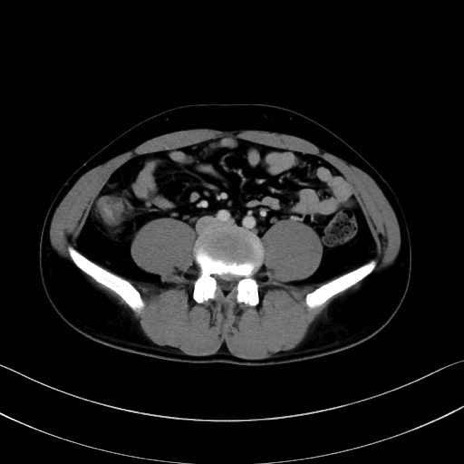

大腰筋 (Psoas major)

腸骨筋 (Iliacus)